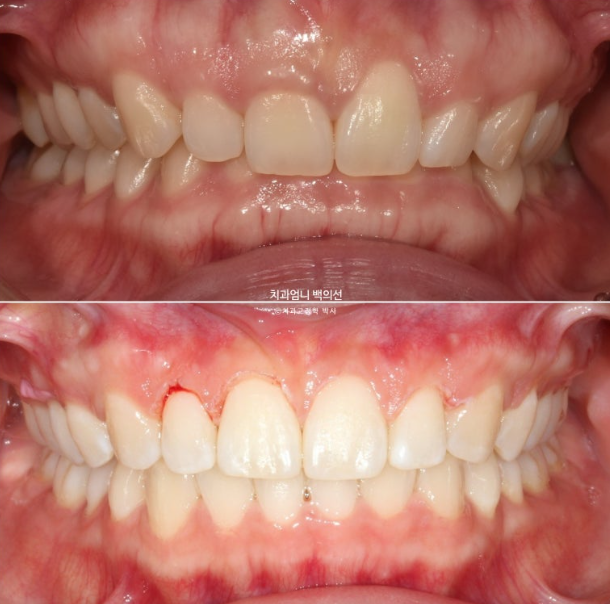

과개교합은 개선이 되었지만 잇몸 비대칭은 그대로입니다.

이 부분은 해결하기 위해 잇몸성형을 진행했습니다.

25.01

잇몸성형 직후 사진입니다.

잇몸이 부어있던 곳에서만 피가 조금 나고 다른 곳은 출혈이 없습니다.

잇몸 라인의 대칭성은 미소 심미에서 중요합니다.